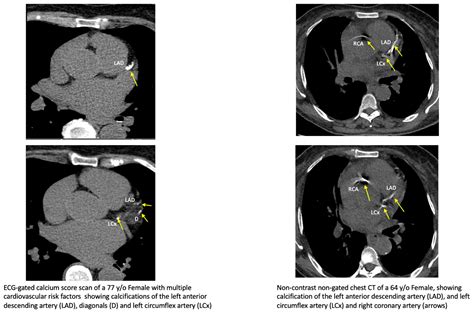

Coronary Artery Calcium scoring is a specialized type of computed tomography (CT) scan that focuses on the heart. Unlike traditional CT scans, CAC scoring specifically looks for calcium deposits in the coronary arteries. These deposits are a sign of atherosclerosis, a condition where plaque builds up in the arteries, narrowing them and increasing the risk of heart attacks and strokes.

During a CAC scan, the patient lies on a table that slides into a CT scanner. The scanner takes multiple X-ray images of the heart from different angles. A computer then processes these images to create a detailed picture of the coronary arteries. The amount of calcium in the arteries is measured and given a score, known as the Agatston score.